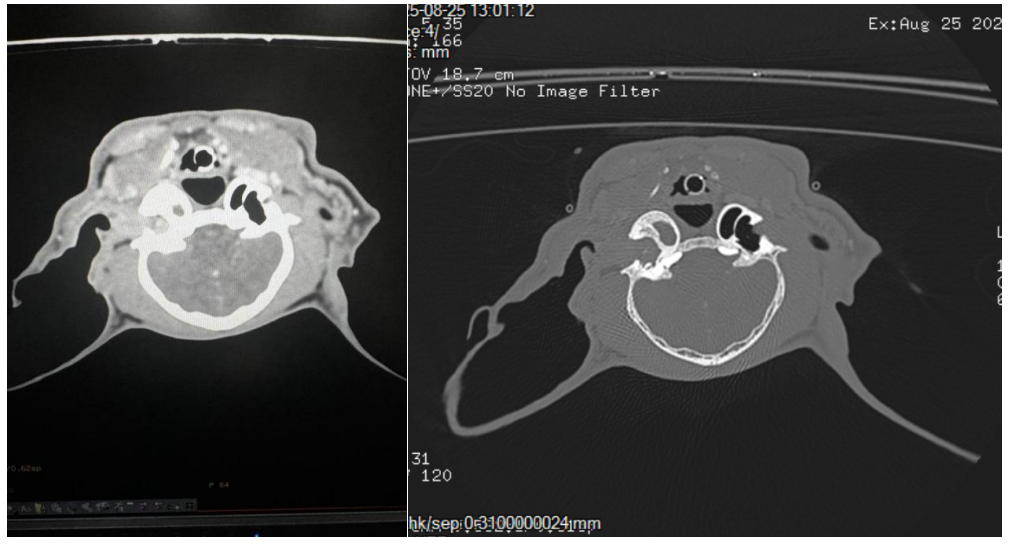

第一步:术前ct检查耳道内可见增生阻塞耳道,鼓室泡内可见积液

image.png